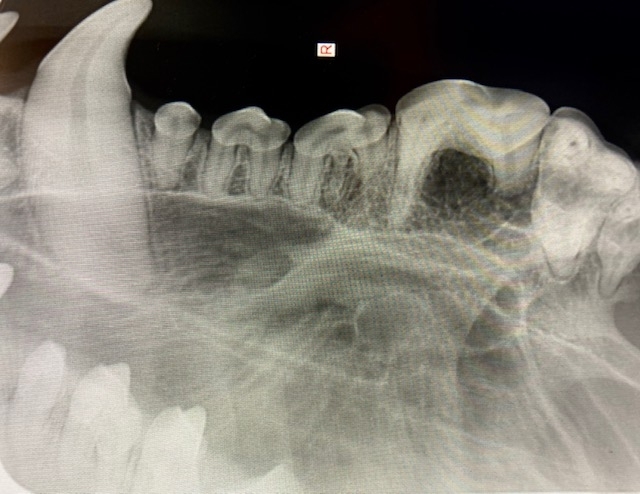

- 牙科X 光;